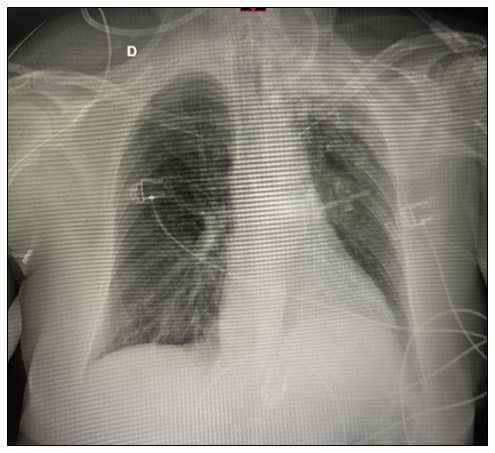

The surgical team performed a bladder catheterization. Balanced general anesthesia was maintained with sevoflurane 2%, dexmedetomidine 0.2 mg/kg/h, ketamine 15 mg, magnesium 2 g, 2,500 ml of crystalloids infused, and 1,300 ml of urine was administered without complications, with a total procedure duration of 7 hours. After extubation, she remained eupneic for 30 minutes in room air and was transferred to the post-anesthesia care unit (PACU), suddenly developing tachydyspnea, stridor, cyanosis, agitation and diffuse coarse rhonchi on pulmonary auscultation. An oxygen mask of 6 l/min was placed, and the condition worsened, and tracheal intubation was performed after administration of fentanyl (100 µg), lidocaine (80 mg), propofol (50 mg), and rocuronium (50 mg) under direct laryngoscopy, with a 7.0 orotracheal tube with cuff. Post-intubation blood gas analysis was performed with a PaO2/FiO2 ratio of 175, and improvement in mechanical ventilation parameters, and a significant drop in lung compliance with a chest X-ray showing diffuse interstitial infiltrate (Figure 2).

Figure 2 Chest X-ray after intubation in the ICU.